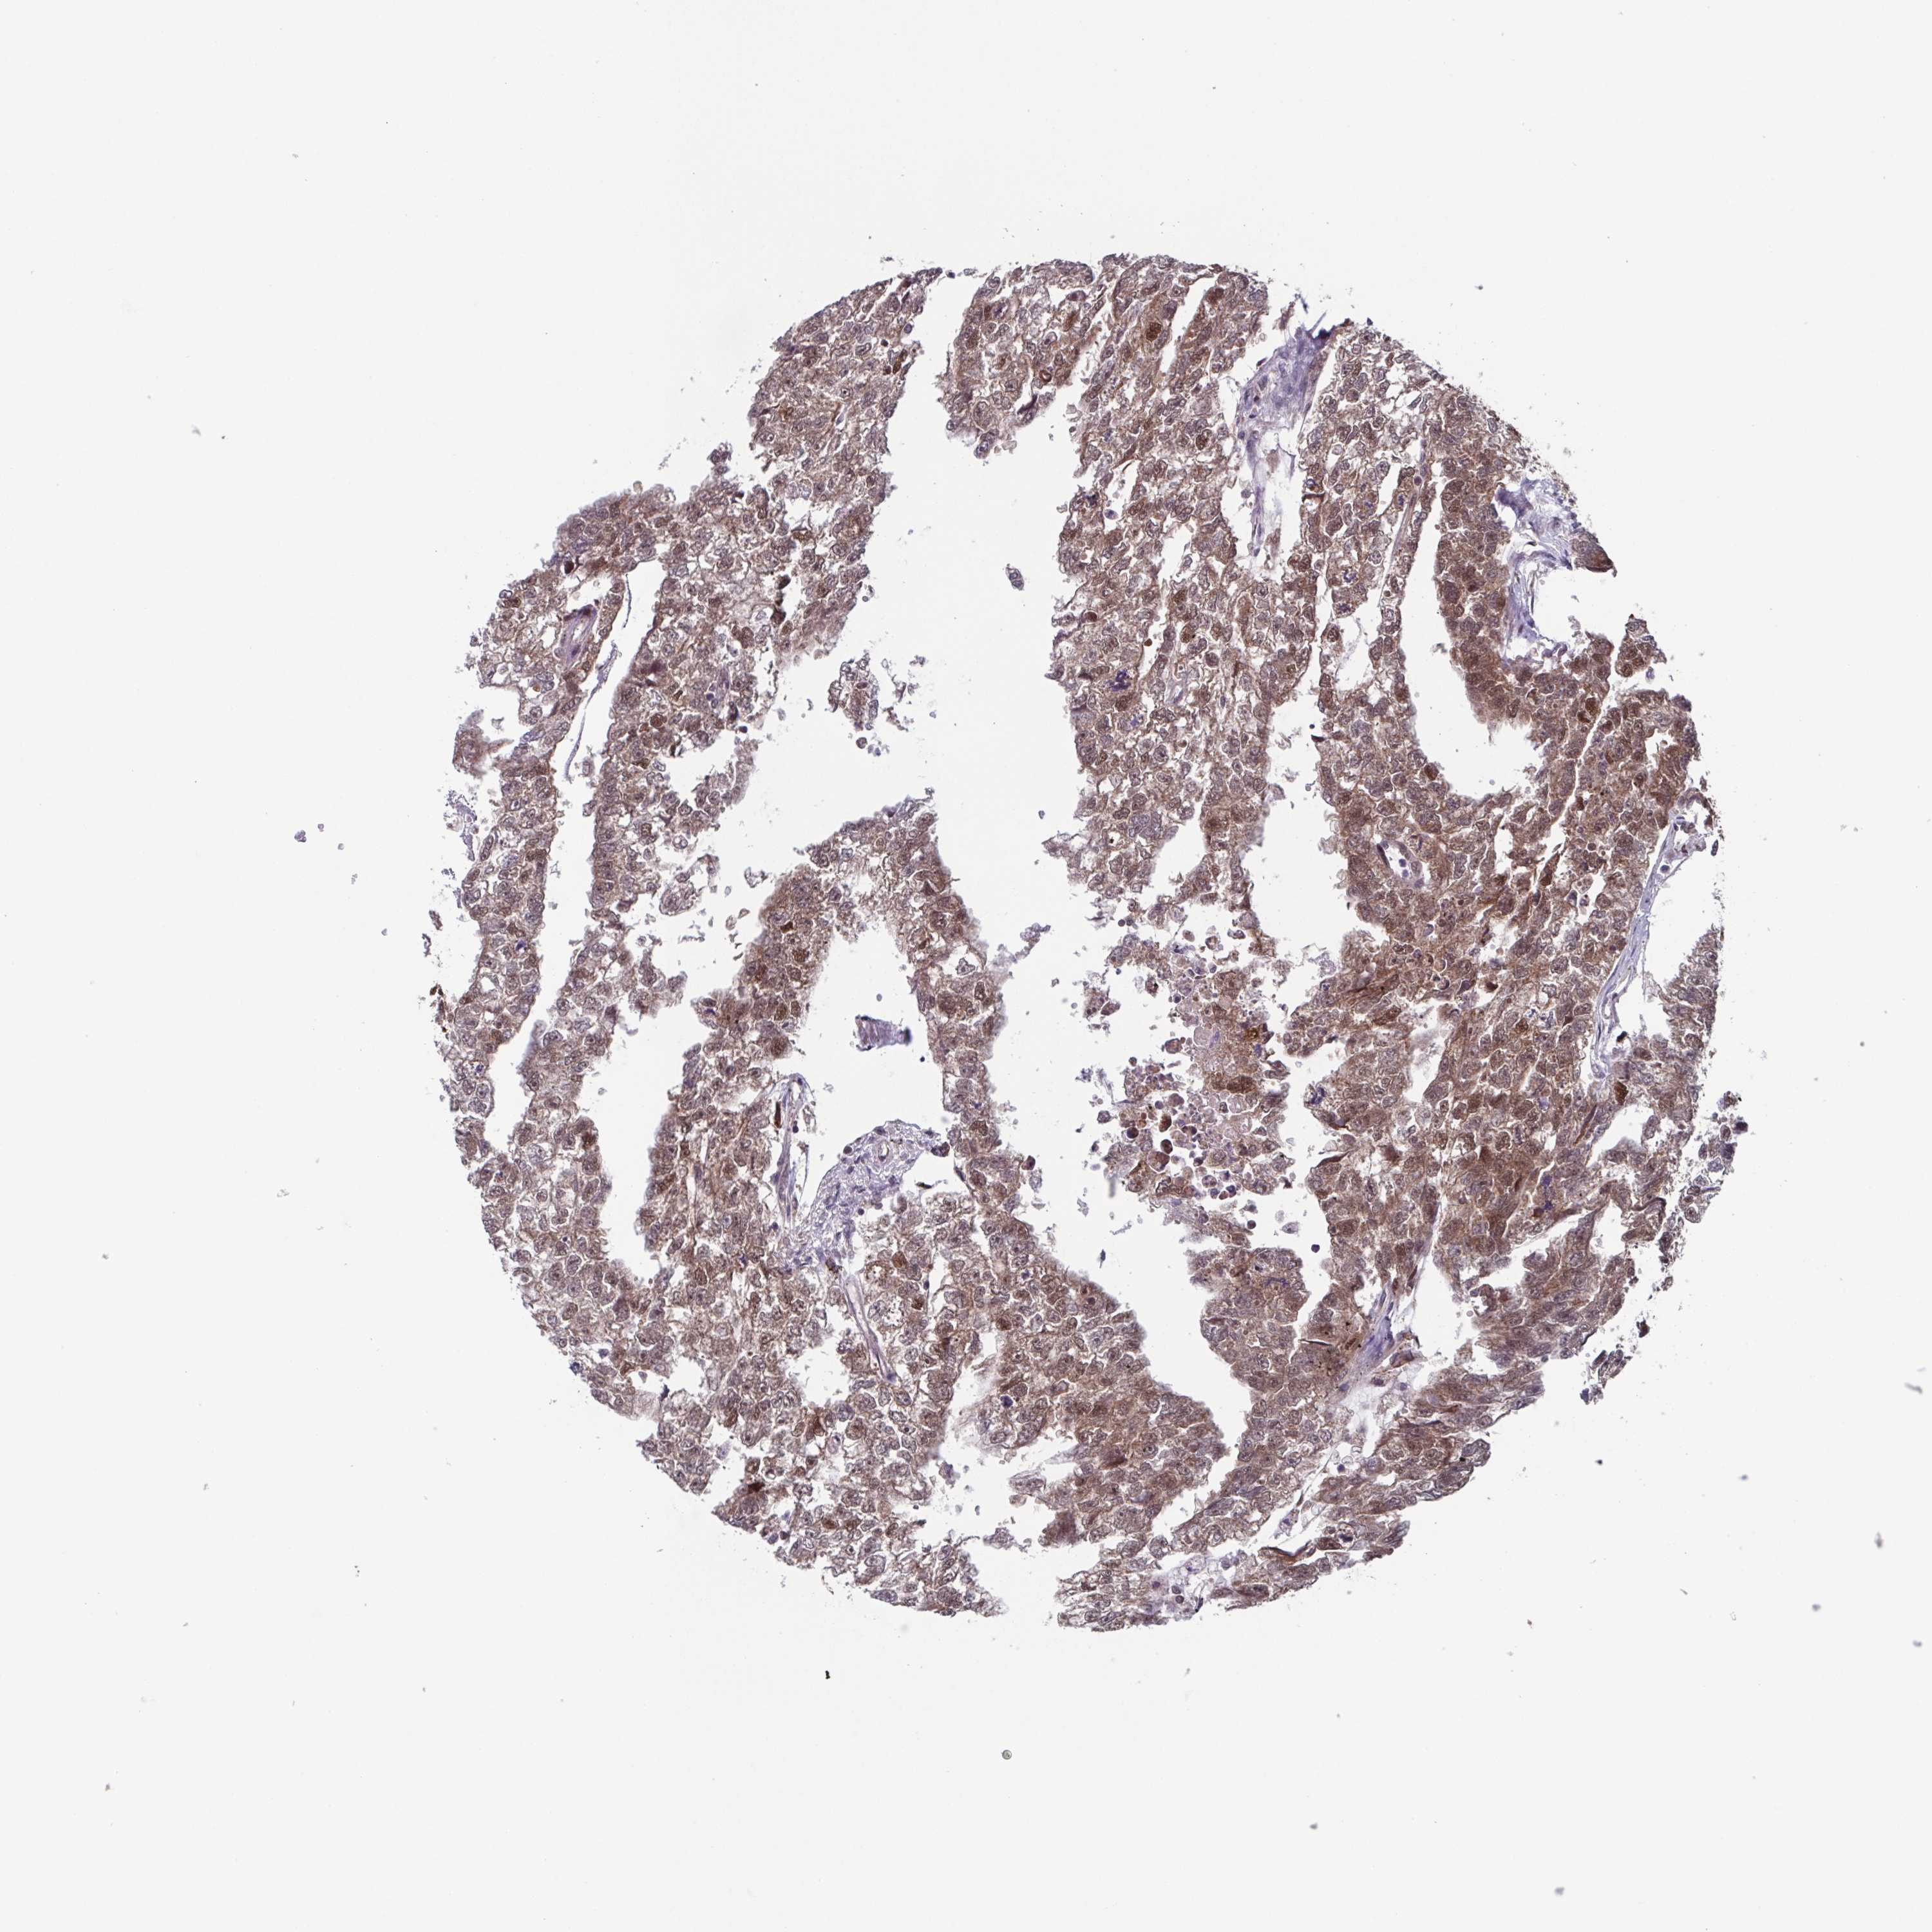

TESTIS CANCER - Protein expressioni

A mouse-over function shows sample information and annotation data. Click on an image to view it in a full screen mode. Samples can be filtered based on level of antibody staining by selecting one or several of the following categories: high, medium, low and not detected. The assay and annotation is described here.

Note that samples used for immunohistochemistry by the Human Protein Atlas do not correspond to samples in the TCGA dataset.

Antibody stainingi

Antibody staining in the annotated cell types in the current human tissue is reported as not detected, low, medium, or high, based on conventional immunohistochemistry profiling in selected tissues. This score is based on the combination of the staining intensity and fraction of stained cells.

Each image is clickable and will lead to virtual microscopy that enables deeper exploration of all samples and also displays staining intensity scores, fraction scores and subcellular localization as well as patient and tissue information for each sample.

Antibody HPA023010

Antibody HPA052380

Staining

High

Medium

Low

Not detected

Intensity

Strong

Moderate

Weak

Negative

Quantity

>75%

75%-25%

<25%

None

Location

Nuclear

Cytoplasmic/membranous

Cytoplasmic/membranous,nuclear

Carcinoma, Embryonal, NOS

Seminoma, NOS

Teratoma, malignant, NOS